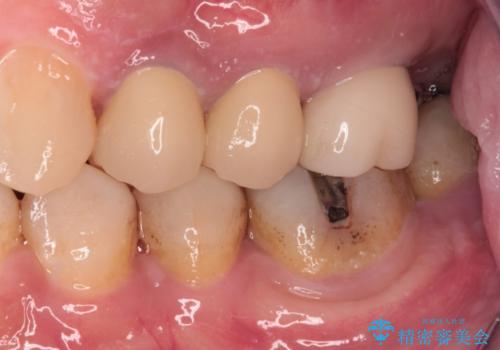

- 以前根管治療を行い、クラウンにする必要があると言われたものの、そのままに放置してしまったとのことで来院された患者様です。

根管治療を行った歯には特に症状がないため、速やかにオールセラミッククラウンにて補綴治療を行うこととしました。

補綴治療前は食後はいつもものが挟まっていたそうですが、補綴治療後はものが挟まる悩みから解放されたとのことでした。